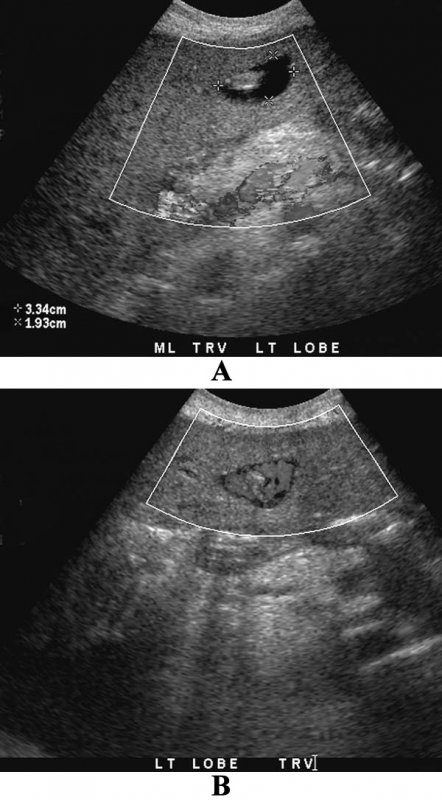

УЗИ брюшной полости: артефакт ложного потока при асците

Фото 5. УЗИ брюшной полости: артефакт ложного потока при асците. А – поперечное изображение в режиме серой шкалы через серповидную связку отмечается анэхогенная жидкость, которая ее окружает. В – цветная допплерография демонстрирует окрашенную жидкость

Артефакт ложного потока позволяет выявить течение жидкости или баллотирование (колебание или смещение анатомического образования в какой-либо полости организма) в местах скопления жидкостей (например, при абсцессе или гематоме, которые могут симулировать объемные образования).